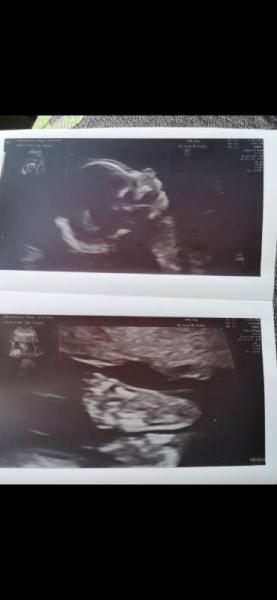

Guten Abend ihr lieben :) Ich hatte heute den Termin zur Feindiagnostik und hab endlich mal gute Neuigkeiten. Dem Baby geht's blendend und war sehr aktiv... Der Arzt war fast schon etwas genervt, weil er nichts länger als 30 Sek anschauen konnte, bis sie sich weggedreht hat. Ja, ich schreibe "sie", denn wir haben auch endlich unser entgültiges Outing... Wir sind team Rosa Außerdem hat meine Plazenta keine komplizierten Lage mehr sondern hört vor dem Muttermund auf und meine Zervix ist auch im grünen Bereich. Hab euch mal das wunderschöne Bild ran gehängt. Bei den Füßen musste ich weinen und sogar mein Mann musste sich 2-3 Tränchen "wegdrücken" Morgen hab ich Wochenwechsel in die 22. Woche

Bild zu Endlich gute Nachrichten - Forum für Januar - Mamis